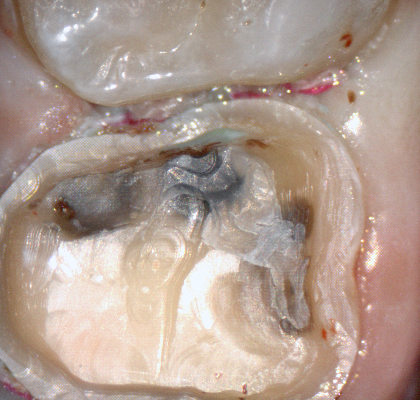

A shoulder bur of .8 mm thickness can help you reduce the interproximal areas as well as the buccal and lingual margin lines. Before finishing the prep, place hemostatic agent like expasyl in the sulcus and place retraction cord. while it is setting, check your reduction. If you need more space, now is the time to reduce some more.

Once you have adequate clearance, retraction, and hemostatis, you can readily image and find your margins in the CAD software